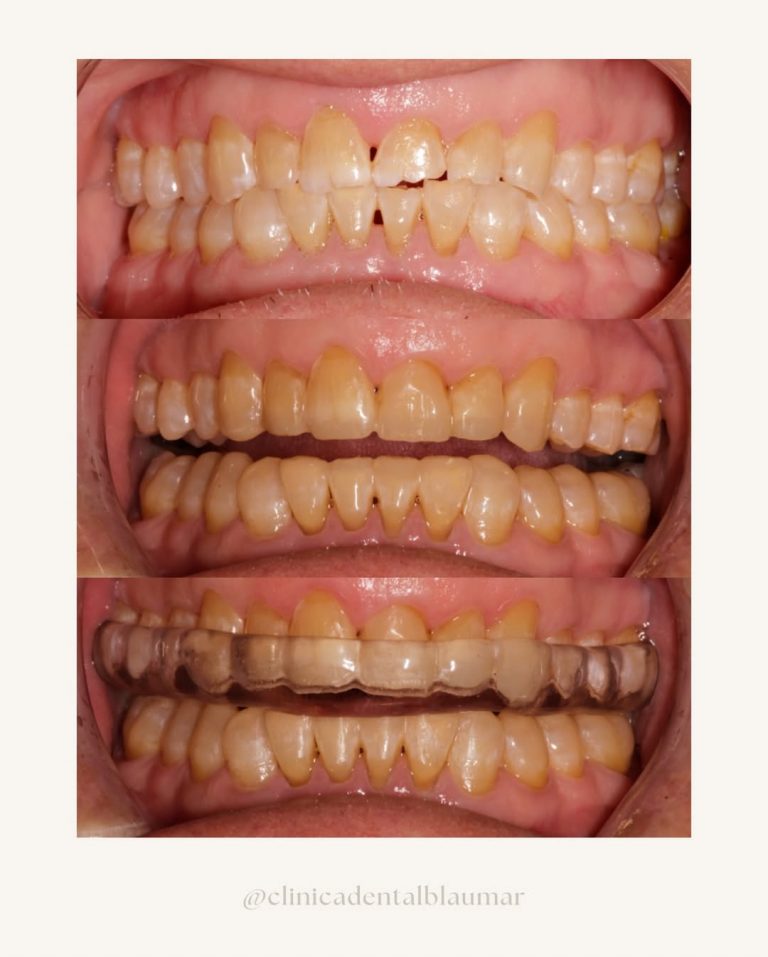

Casos reales de antes y después

Cada sonrisa tiene una historia. En Clínica Dental Blaumar te mostramos casos reales de pacientes que confiaron en nosotros para mejorar su salud y su estética dental. Antes y después, procesos y resultados explicados con claridad, para que veas cómo trabajamos: con planificación, precisión y un trato cercano de principio a fin.